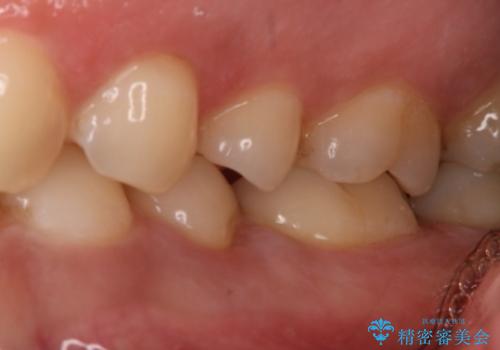

保険の材料と比較して、セラミックは劣化しにくく審美性も高い材料です。

- 左下6番の治療のやり直しを希望し来院された患者様です。

自費の治療を希望されたため切削量・形態を考慮し、セラミックインレーでの治療を計画しました。